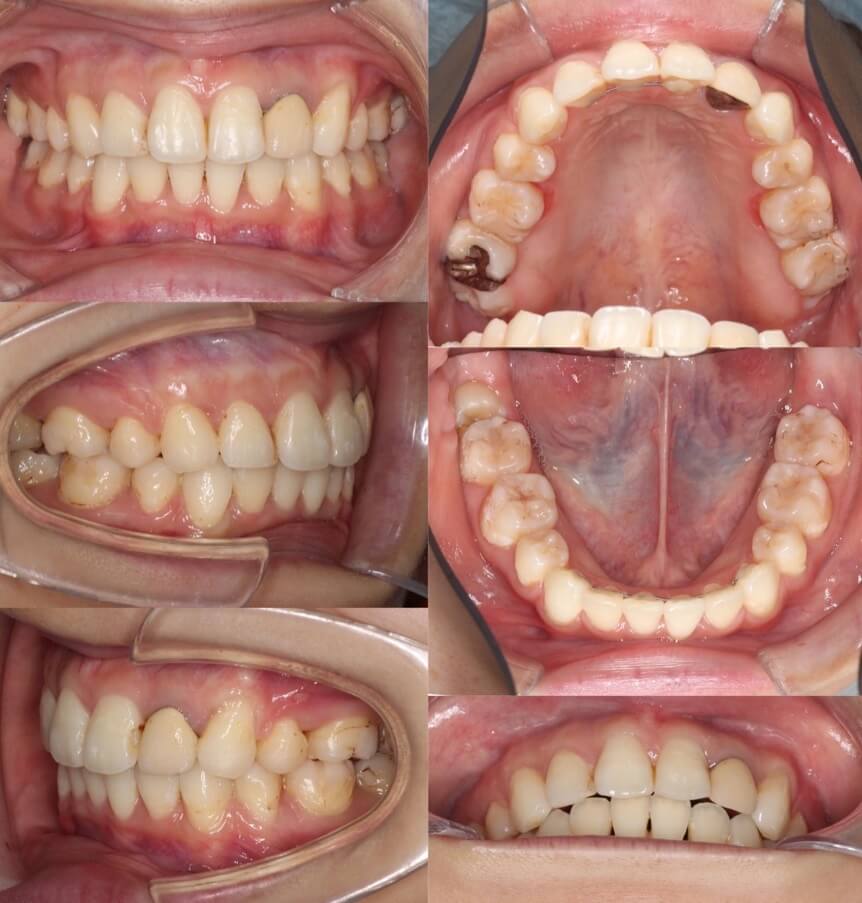

「開咬ならマウスピースも可能」

20代女性・マウスピース型装置・前歯傾斜型

マウスピース型矯正治療は前歯の歯根の後方移動が難しく、口ゴボ症例の適応症は少ないと言えます。その中で、開咬症例は数少ない適応症です。外開きになっている前歯を傾斜移動をコントロールしながら、後方移動させました。

<症例概要> 難易度:★★★★☆

主訴:口元の突出と前歯のかみ合わせ

年齢・性別:20代女性

住まい:千葉県八千代市

症状:開咬・上下顎前歯唇側傾斜・叢生

治療方針:抜歯空隙の閉鎖(中等度固定)

治療装置:マウスピース型矯正装置(アライナー装置)

抜歯:上下左右4番(計4本)

治療期間:2年1か月

アライナー枚数:29+27+20ステージ

リテーナー:上下クリアタイプ+フィックスタイプ

治療費用:990,000(税込)

代表的副作用:痛み・治療後の後戻り・歯根吸収・歯髄壊死・歯肉退縮